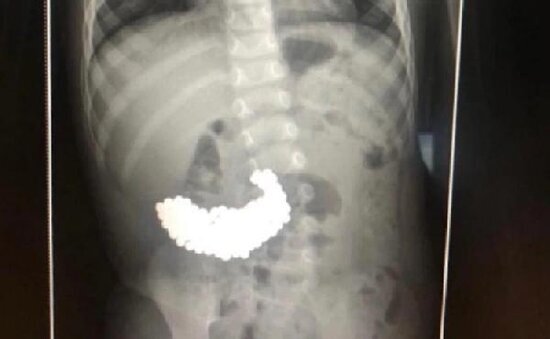

Rentgen edildikdən sonra uşağın mədəsində rəngli maqnit topların olduğu müəyyən edilib.

Əməliyyat edilən uşağın bağırsağından 209 maqnit topu çıxarılıb.